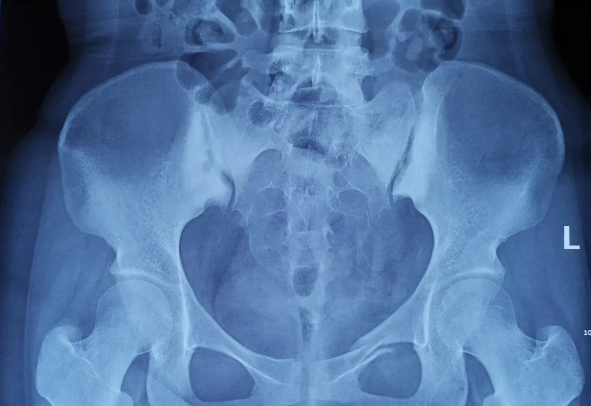

2025-02-28智匯天璣|高齡不是禁區(qū)!北京積水潭醫(yī)院智能骨科機(jī)器人助力90歲骨盆骨折患者重獲行走

由北京積水潭醫(yī)院院長(zhǎng)蔣協(xié)遠(yuǎn)、智能骨科研究型病房主任王軍強(qiáng)帶領(lǐng)的智能骨科團(tuán)隊(duì),運(yùn)用骨科機(jī)器人輔助經(jīng)皮骨盆通道螺釘置入技術(shù),成功救治了一名90歲高齡的骨盆骨折患者。 -

2021-01-06天璣骨科手術(shù)機(jī)器人落戶(hù)南昌市第一醫(yī)院,助力骨盆骨折閉合復(fù)位內(nèi)固定術(shù)順利完成

近日,天璣?骨科手術(shù)機(jī)器人落戶(hù)南昌市第一醫(yī)院,助力骨盆骨折閉合復(fù)位內(nèi)固定術(shù)順利完成。作為江西省首先采用5G引導(dǎo)下的骨科機(jī)器人手術(shù),天璣?骨科手術(shù)機(jī)器人用它的“透視眼”,以三維影像掃描進(jìn)行深層三維空間精準(zhǔn)定位,為患者“量身定做”了最理想、最安全的教科書(shū)般通道,完成了復(fù)雜骨盆骨折微創(chuàng)治療一次性完美置釘及腰椎骨折微創(chuàng)經(jīng)皮置釘?shù)氖仔悖蔀榻魇」强瓢l(fā)展的標(biāo)志性事件,同時(shí)也是江西省骨科步入新型數(shù)字智慧骨科時(shí)代的重要里程碑事件。 -